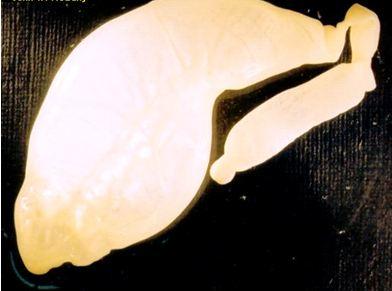

| 4. Echinococcus granulosus

This is a very short dog tapeworm, whose main significance is that the larval stage forms large multiple hydatid

cysts in the intermediate hosts, including humans. These cysts are located in the liver and lungs and can grow to a very large size indeed. People living in close association with dogs are especially at risk.